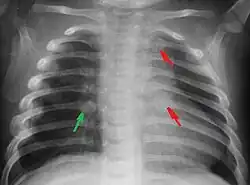

Fractures

Les enfants physiquement maltraités peuvent souffrir de fractures, particulièrement aux côtes[11].

Syndrome du bébé secoué. Secouer un bébé est une forme commune de maltraitance enfantine qui peut résulter à des dommages neurologiques irréversibles (80 % des cas) ou la mort (30 % des cas)[59]. Ces dégâts sont le résultat d'une hypertension intracrânienne (pression élevée dans le squelette) après une hémorragie interne cérébrale, des dégâts à la moelle épinière et au cou, et de fractures des os et des côtes (Institute of Neurological Disorders and Stroke, 2007).